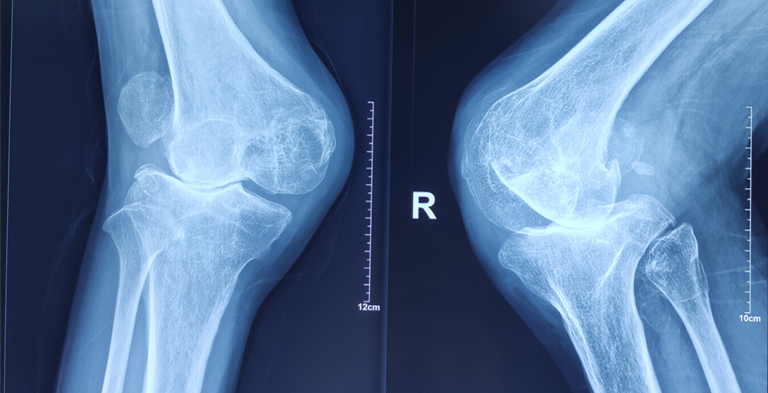

- 骨二科成功完成一例高难度人工膝关节置换术

- 我院骨伤二科李崇鑫副主任医师成功完成一例双侧膝关节重度外翻人工膝关节置换术。 患者苏某,男,63岁,17岁时双膝关节被土方塌伤,当时由于条件有限,未及时治疗。现如今畸形